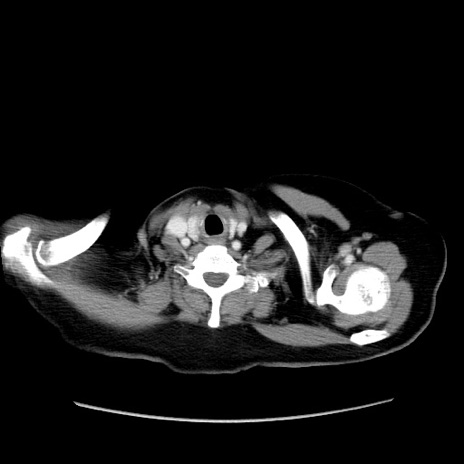

症例19(横断像)

【症例】80歳代女性

【主訴】下腹部痛

【現病歴】約8時間前より下腹部痛の出現あり、救急外来受診。

【既往歴】両側付属器切除

【身体所見】意識清明、下腹部正中に手術痕あり、その部位に一致して圧痛と反跳痛あり。腸蠕動音は亢進。

【データ】WBC 9300、CRP 0.15